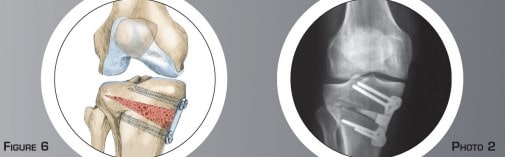

Le genou correspond à l’articulation entre la partie basse du fémur et la partie haute du tibia. Les surfaces articulaires de glissement sont recouvertes de cartilage (figure n°1).

Les ménisques sont des petits coussinets en forme de croissants situés entre le cartilage du fémur et celui du tibia. Ils améliorent le contact et jouent un rôle d’amortisseurs entre le fémur et le tibia.

L’arthrose débutante interne est l’usure du cartilage présente entre la partie interne du fémur et du tibia (figure n°2 et photo n°1). La morphologie du membre inférieur en est souvent la cause principale. Sur une forme incurvée, tout le poids du corps passe plutôt par la partie interne du genou (figure n°3). Cette surcharge aboutit à l’usure prématurée du cartilage et du ménisque.